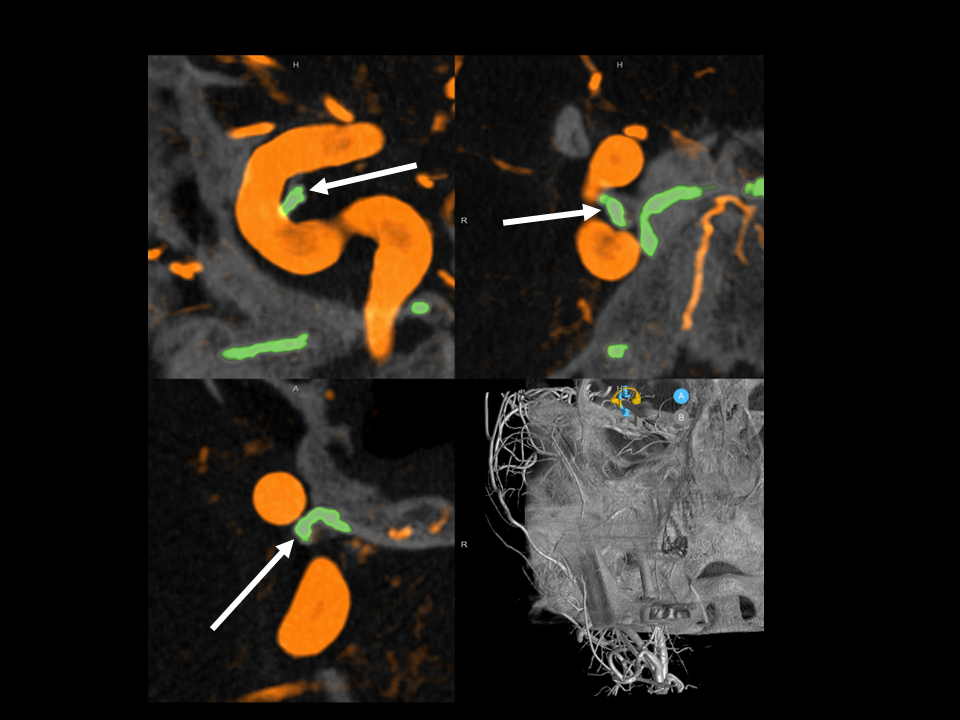

CSF Lymphatic Fistula

A fantastic and unique case